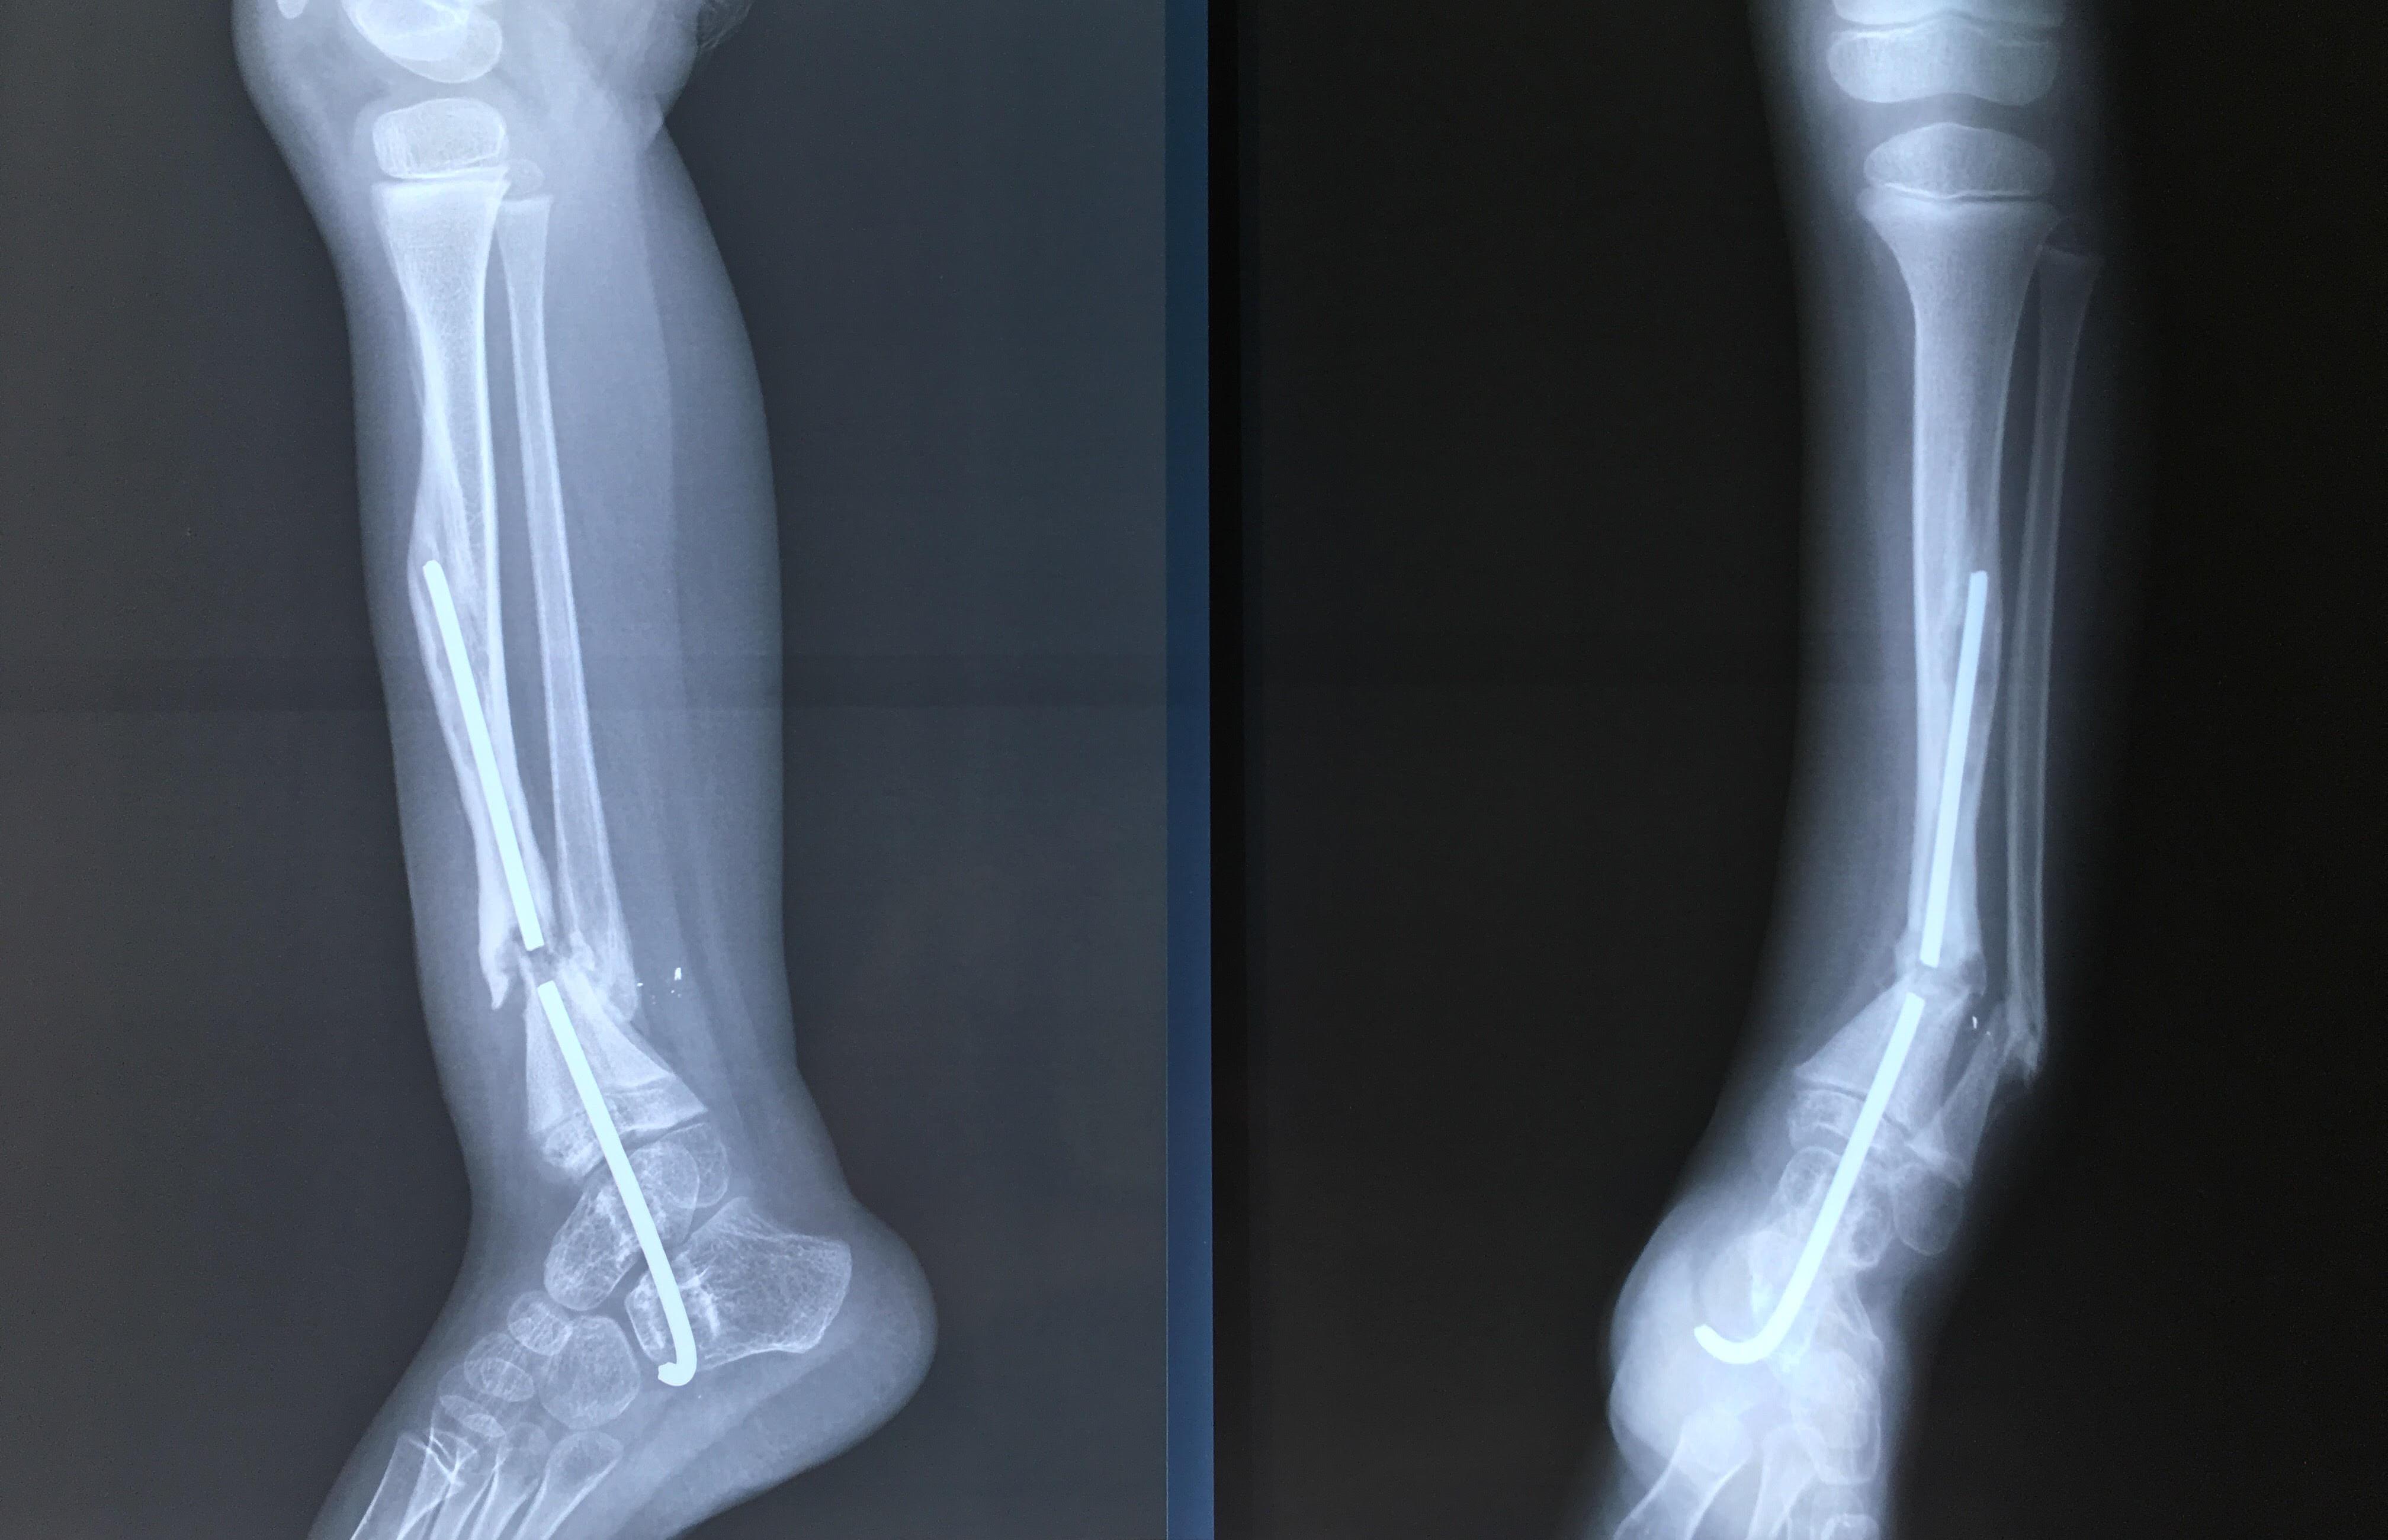

Phẫu thuật thành công ca bệnh hiếm gặp...khớp giả bẩm sinh xương chày

26/06/2019 17:00

Đã xem: 3380

Bệnh viện Chấn thương- Chỉnh hình Nghệ An, vừa phẫu thuật thành công cho bệnh nhi khớp giả bẩm sinh xương chày